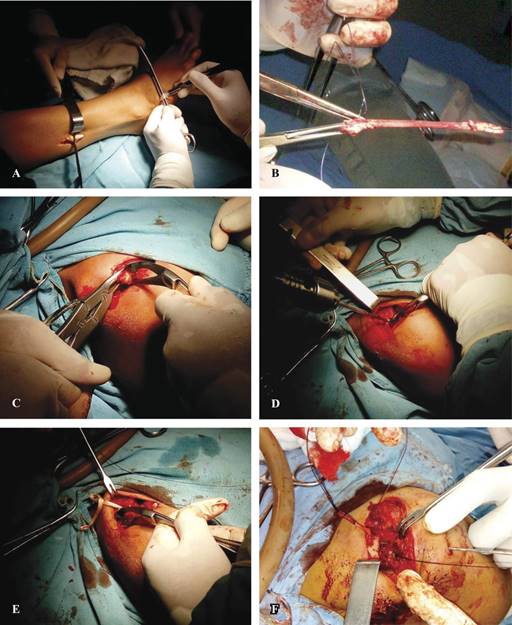

En el presente estudio se utiliza el tendón del peroneo lateral corto debido a su fácil obtención y a que su ausencia no ocasiona alteración funcional alguna (Figura 1); es un tendón de grosor y resistencia similar al semitendinoso y que ha sido utilizado por otros autores en la plastía de los ligamentos acromioclaviculares,42 pero que no existen reportes de su uso en la plastía de los coracoclaviculares. Se llevó a cabo también la resección de un segmento de la parte externa articular de la clavícula con la finalidad de evitar la fricción entre los dos extremos óseos de la articulación acromioclavicular y la posibilidad de dolor al elevar el brazo después de la cirugía. Dadas las características anatómicas y biomecánicas de la articulación, la resección clavicular no la afecta en su función.

Figura 1: A) Toma del injerto del peroneo lateral corto. B) Preparación del injerto. C) Resección del extremo clavicular. D) Perforación de los orificios en la clavícula. E) Paso del injerto tendinoso por los orificios. F) Fijación de la clavícula con un clavo de Steinmann.

Primero: obtención del injerto libre del tendón peroneo lateral corto mediante dos abordajes, uno en su inserción en la base del quinto metatarsiano y el otro a nivel de su unión miotendinosa en el tercio distal de la pierna.

Segundo: resección de 1.5 cm del borde articular externo de la clavícula mediante abordaje de Roberts sobre la articulación acromioclavicular.

Tercero: elaboración de dos perforaciones en la clavícula a 1.5 y 3.0 cm del borde clavicular después de la resección, sitios de inserción de los ligamentos coracoclaviculares.

Cuarto: paso del injerto tendinoso por debajo de la apófisis coracoides.

Quinto: paso de cada extremo del injerto tendinoso previamente cruzado por los orificios elaborados en la clavícula.

Sexto: alineación del borde externo clavicular al acromion, con leve sobrecorrección.

Séptimo: estabilización del acromion a la clavícula mediante un clavo de Steinmann de 5/64’’ (Figura 2).

Octavo: sutura de los extremos del tendón sobre el borde superior de la clavícula mediante puntos de sutura no absorbible.